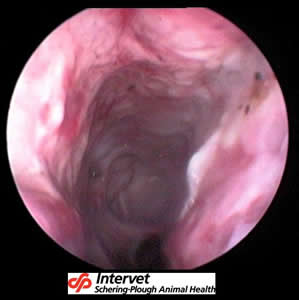

D’autres méthodes existent mais sont inutilisables en routine (Rhinoscopie, IRM, scanner…) : elles illustrent cependant bien les dégâts faits par la Rhinite Atrophique :

![]() |

Image par endoscopie du cochon des photos précédentes. La paroi nasale est inflammée et bosselée, et on ne distingue plus les volutes nasales. |